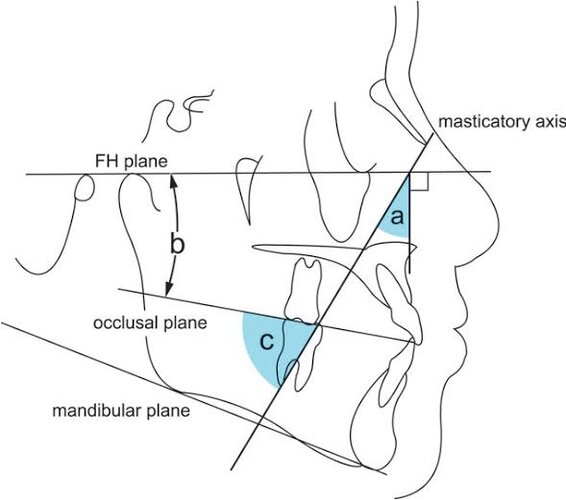

When u have a bad nose but also want to do a surgery that includes Le Fort osteotomy, u should first do Le fort since moving the maxilla can have an effect on the nose right?